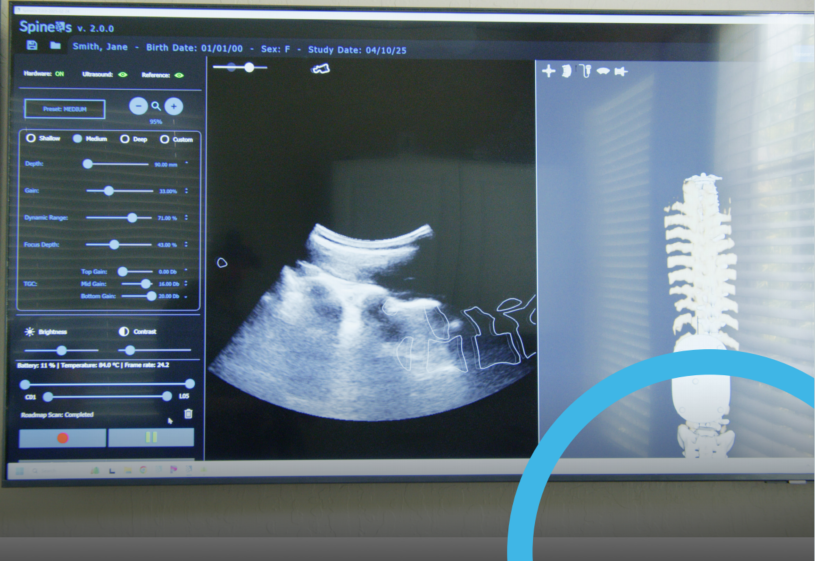

Schlenger为3D脊柱超声成像配备了OptiTrack系统,通过该系统能够将骨骼位置以亚毫米级的精度进行定位,进而通过图像拼合进行三维重建,最终将高精度的骨骼数据实时传输到超声图像中,为脊柱超声的3D成像提供了可靠的依据。Schlenger提到,“OptiTrack系统每秒可以处理超过22帧,同时可以快速分析一整帧图像,并在3D环境中准确重建,这一切几乎是实时完成的,非常令人惊叹!”

最终,Schlenger通过OptiTrack系统的精准定位与2D超声设备结合,在扫描患者时,AI能够只识别骨骼结构,并将通常杂乱的2D超声图像转化为精美的脊柱3D图像。即使在超声图像上没有任何显示,AI算法也能够识别出实际的骨骼结构,形成了精准且清晰的脊柱3D骨骼图像。这一实验的成功,标志着OptiTrack在3D超声成像能够在脊柱诊断中得到应用,同时也将为肝脏诊断、肾脏评估、动脉检查等在内的3D成像开辟新的可能。此外,通过OptiTrack进行追踪成像除了具备更为精准、立体、清晰的优势,其另一大特点是可以消除辐射暴露的影响,为医疗检测提供更安全的解决方案,未来广泛应用于医疗检查中将大大减少因影像检测而带来的癌症风险。